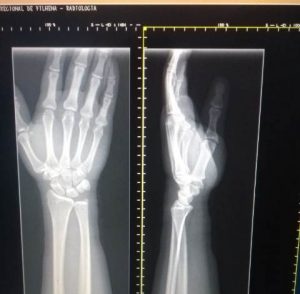

Um paciente que usou os serviços do Hospital Regional de Vilhena manhã desta segunda-feira, 9, enviou áudio à redação do site relatando o que seria uma situação interessante: servidores da unidade de saúde orientam pacientes a usar o celular e tirar foto das imagens captadas pelo aparelho de Raio X para que depois seja mostrado ao médico.

Além do áudio, o paciente enviou a fotografia tirada no centro de Raio X, o que lhe causou estranheza. Ele afirma que estava faltando filme.

Ele informou ao site que até o médico ficou surpreso quando analisava as fotografias da mão e antebraço.

“O técnico da sala de Raio X disse que faltava filme e então pediu para bater uma foto com meu celular e depois que fosse mostrar ao médico. Fiquei surpreso. O que me informaram que é estava faltando filme”, revela.

Ouvido pela reportagem do Extra de Rondônia, o diretor do HR, Faiçal Akkari, disse, porém, que filme tem no HR para quem precisar, mas que o uso do celular é uma forma de “economia e modernidade” no serviço público.

“O médico pode examinar, através das imagens captadas pelo celular, se há alguma fratura ou não. Agora, se o caso for mais complexo e solicitar as imagens no filme, fazemos questão de imprimir. É uma questão de economia e modernidade. Dá para ver a imagem na tela do celular e até ampliar se for necessário. E tem mais: daqui a uns dias, o médico vai abrir a imagem direto na sala usando tablete. Temos que nos adequar à modernidade”, esclareceu, ao dizer que cada filme custa R$ 15,00.